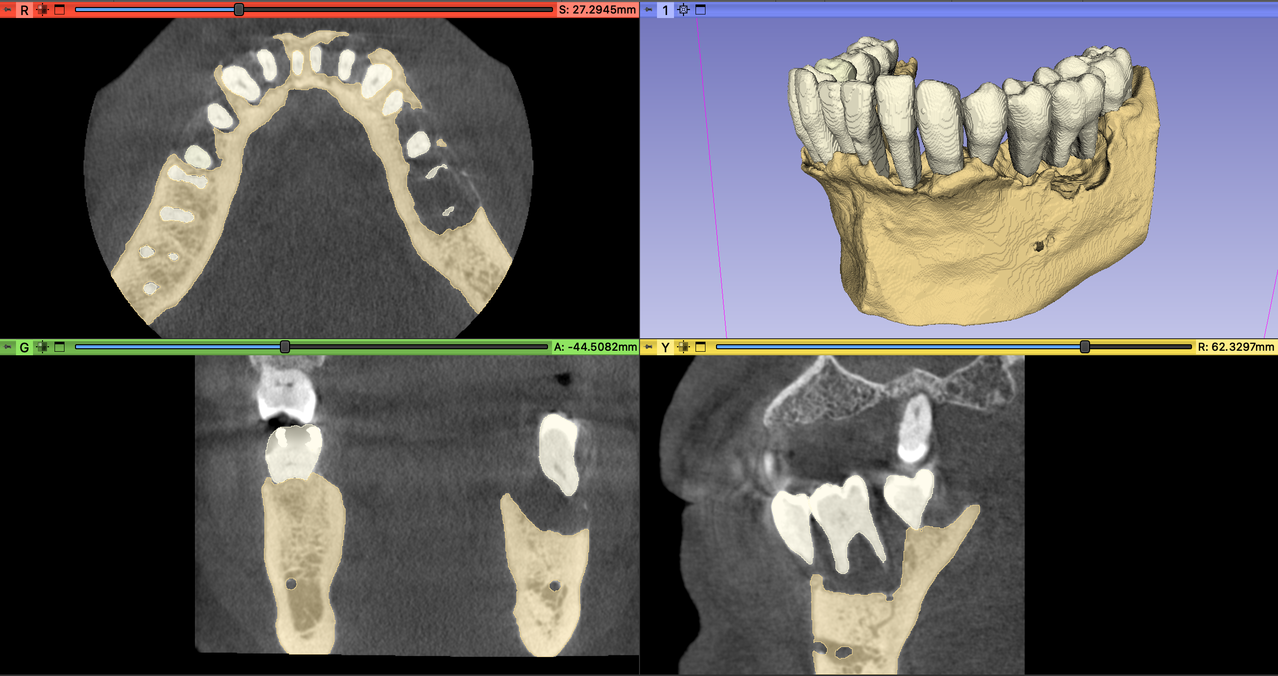

Example segmentation:

A three-dimensional visualization of dento-alveolar structures can enhance the surgical planning process, however currently there are no reliable fully automated segmentation methods available to acquire realistic 3D virtual models of teeth and alveolar bone. A time consuming semi-automatic method has previously been utilized for diagnostic purposes and surgical planning of regenerative-reconstructive surgical procedures in periodontology and oral surgery.

The aim of this project is to develop an automatic method utilizing MONAI Label to speed up segmentation process of dento-alveolar structures on cone-beam computed tomography datasets.

- Objective A. To develop a fast and relible segmentation method that is capable of the separate 3D reconstuction of teeth and alveolar bone on CBCT datasets of periodontally involved patients